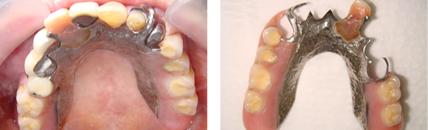

拆下牙橋前

拆下牙橋後